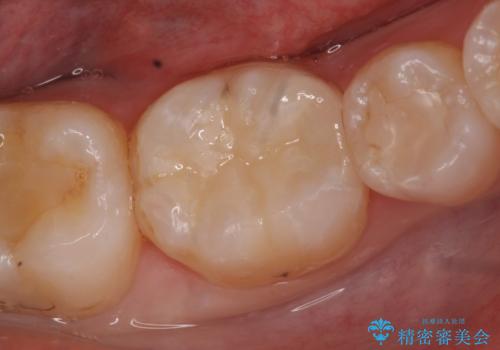

- 右下4番の歯に違和感を自覚して来院された患者様です。レントゲンで歯の内部吸収が認められたため、抜歯をすることになりました。

右下4番に関してはブリッジ、下あごの奥歯が欠損していたのでインプラントで治療することとなりました。

右下4番の抜歯後に右下3番は精密根管治療を行い、右下3番と右下5番にファイバーコア(土台)を築造し、ブリッジを装着しました。

下顎の両側6番にはインプラント治療をおこないました。